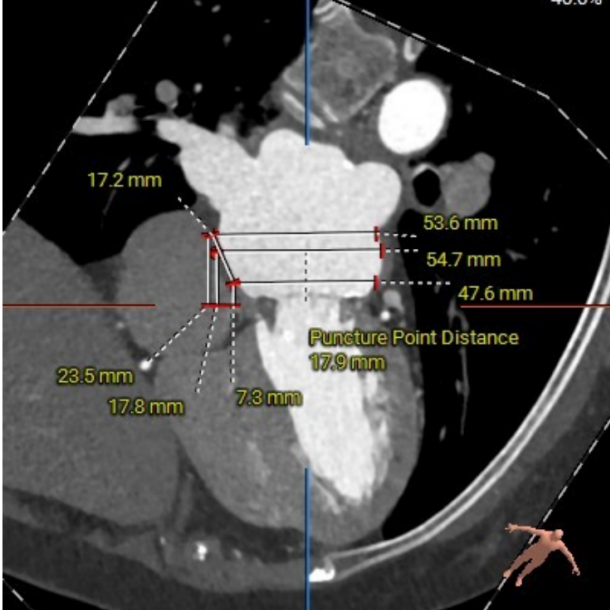

左房53×48mm,靠后下的房间隔穿刺点距二尖瓣高度17.9mm。患者房间隔显著增厚、钙化,房间隔穿刺点较低,考虑房间隔穿刺及器械到位较为困难。